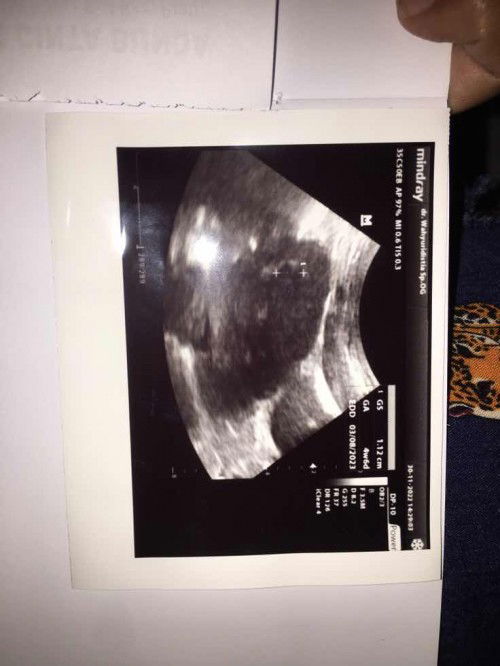

Bun Hasil Usg sama Hpht ko beda yaa?

Bun ini pertama saya USG kenapa hasil USG sama HPHT beda yaa.. di USG usia kandungan 4 week 6 hari, tapi kalo menurut bidan sama aplikasi ini usia kandungan 8 week 3 hari. Jadi hpl nya juga beda kalo USG 3 Agustus, kalo hitungan Hpht bidan sama aplikasi ini hpl nya 10 Juli.. jadi Yg bener Yg mana ya soalnya beda hampir 1 Bln. Agak worry gk sih bun?